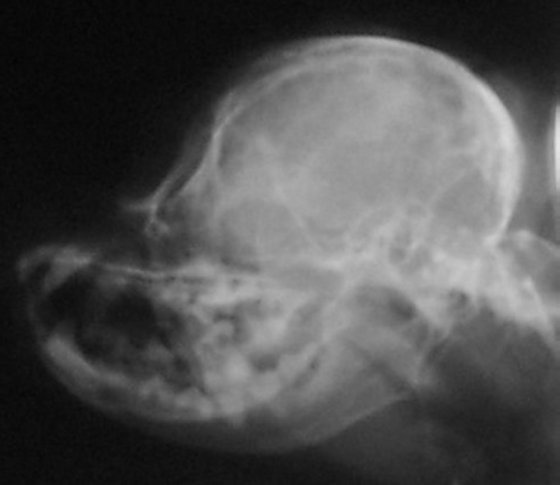

The skull x-ray of a dog with a full cerebellum is below that on

the left and the skull x-ray of a dog with a crushed cerebellum

is shown on the right. You can easily see there is a distinct

difference in the shape of the back of the skull between the two

and why the cerebellum ends up crushed. The most distinct

difference, besides the fact that the skull on the right is

shorter from front to back, is that the occiput sticks out in

the skull x-ray on the left. In the right, that occiput is still

there, but it is more downsloped and blends in with the back of

the skull to the point you can barely see it--almost like

someone took a hammer to the occiput and smashed it in.